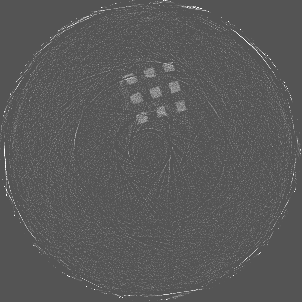

Figure 7 shows a single slice spectral reconstruction of the Mg scaffold. Due to low atomic number of Mg (Z = 12) compared to Ti (Z = 22), the results did not exhibit any significant beam hardening effects. Low energy reconstruction shows good spatial information while high energy ranges are limited by photon noise. In scans involving smaller samples made from low-Z materials like Al or Mg, acquiring low energy quanta in CSM provide high spatial information with minimum or no beam hardening effects. Figure 8 illustrates a single slice spectral reconstruction of the Ti mesh. Similar to the Ti scaffold, streaks are less pronounced in the mid and high energy ranges.